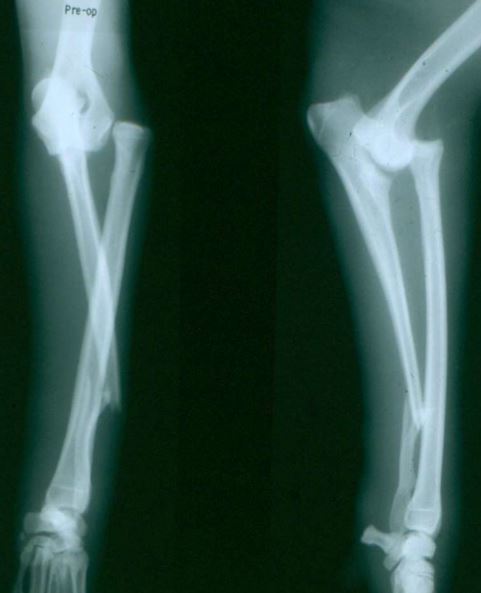

Q

4 month old mixed breed canine

Acute lameness RHL

Classify and assess fracture, and give repair options

A

Transverse fracture of the diaphysis of the tibia

Fx score= 8-10

Repair: ESF, Interlocking nail, External coaptation

Bone plate may be overkill (young patient)